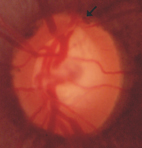

圖二、青光眼的視神經盤

青光眼進行三部曲,依序是視神經萎縮、再來是視野出現缺陷及最後的視力衰退。視神經萎縮通常來自於視神經盤的凹陷,以及視神經纖維的缺陷;3、5年後,視野開始出現缺陷;再過幾年,才會自覺視力衰退。